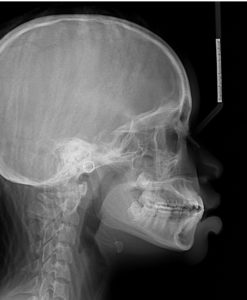

A 14.1 year old African American female presents with a chief concern that “my teeth have a lot of spaces.”